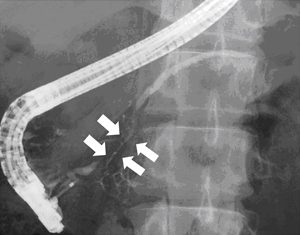

図2 自己免疫性膵炎の膵管造影所見:

矢印で示す部分の膵管が不整に細くなっています

超音波検査やCTで膵臓の全体的あるいは部分的な腫大が認められた場合に、自己免疫性膵炎を疑います(図1)。もうひとつの大きな画像的特徴は膵内を走行する膵管の狭細変化です。この確認のために、まず体に負担をかけずに膵管を描出できる磁気共鳴膵胆管造影(MRCP)を行い、最終的には内視鏡的膵胆管造影(ERCP)により評価します(図2)。